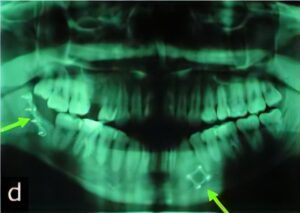

智歯(親知らず)は、全ての歯の中で一番最後に生え、第二大臼歯の後方(一番奥)に生えます。しかし正常に生えることができず、斜めに生えたり、顎の中に生えずに残ってしまうことがあります。

重度の虫歯や、智歯周囲炎、第二大臼歯の虫歯や歯周病の治療のために抜歯が必要になる場合があります。

智歯の抜歯は、生え方にもよりますが、歯肉の切開したり歯牙を分割するなど特殊な抜き方が必要なこともあるため、”親知らずを抜きたくても不安のある方”、“口腔外科医の診察を希望の方”は、ご相談ください。